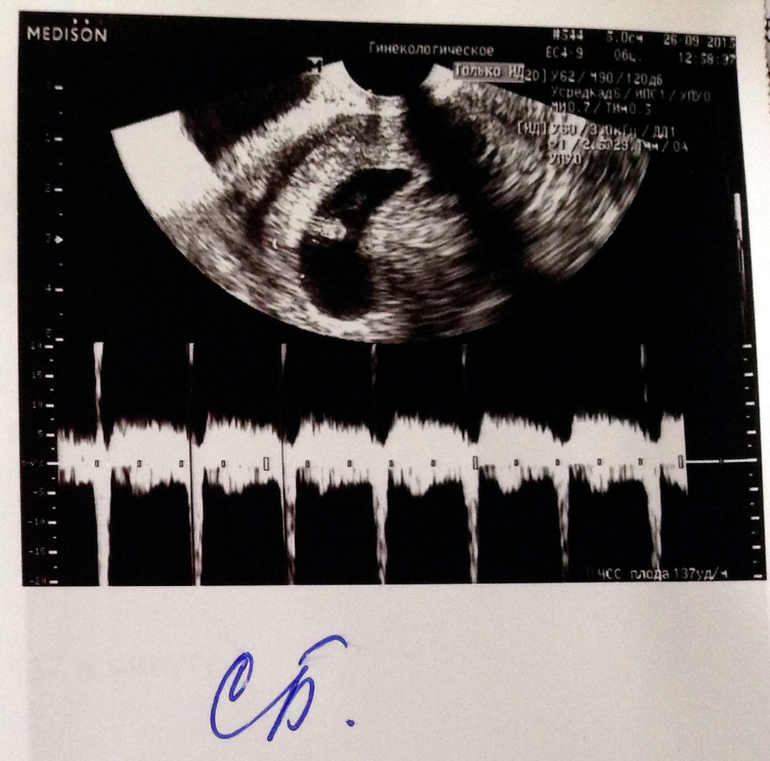

Вот и первые фото малыша :) Еще совсем маленький, 8,3 мм! Срок оказался еще меньше, чем я думала, всего 6 недель и 5-6 дней. Сердечко уже бьется, да так быстро - 137 ударов в минуту. Есть гипертонус передней стенки матки, назначили магний В6, буду успокаиваться. В следующий раз теперь только через месяц идти, 24 октября, будут делать скрининг на генетические патологии, а потом, если все хорошо, встану на учёт :)